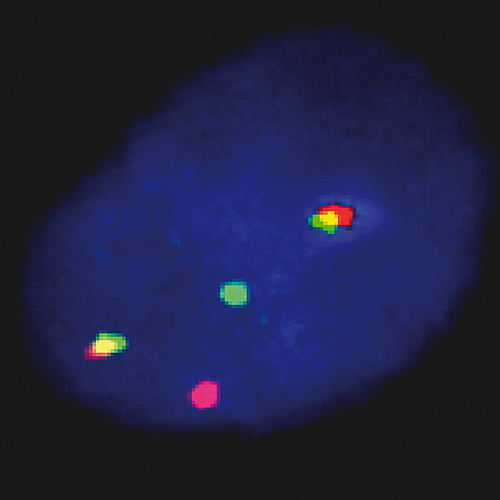

FGFR3 / IGH t(4;14) Fusion probe hybridized to MM patient material showing t(4;14) translocation (2RG1R1G). Image kindly provided by Prof. Jauch, Heidelberg.

The t(4;14) translocation is undetectable by conventional cytogenetics. The breakpoints on chromosome 4 occur within an approximately 113-kb region located in small part of a conserved gene cluster including the transforming acidic coiled-coil protein 3 (TACC3), fibroblast growth factor receptor 3 (FGFR3), and multiple myeloma SET domain-containing protein (MMSET). The translocation is indicative for poor survival and poor response to chemotherapy. The FGFR3/IGH t(4;14)(p16;q32) Fusion specific FISH probe is optimized to detect the reciprocal translocation t(4;14) in a dual-color, dual-fusion assay.